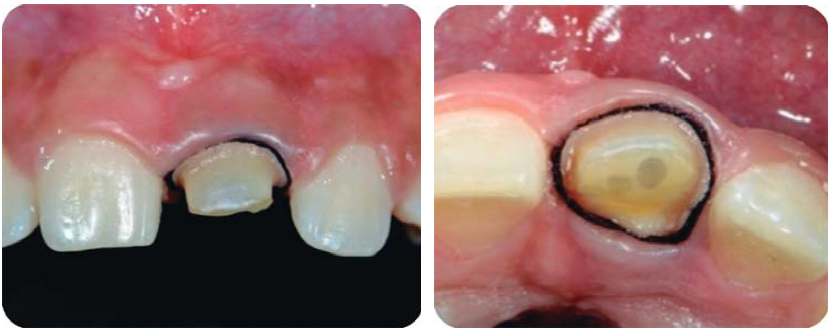

Debido a la evolución de dos días desde el accidente, el paciente presenta dolor e inflamación a la exploración extraoral, durante la exploración intraoral se observa la exposición pulpar de los dientes involucrados (Figura 2) e indica el tratamiento de urgencia a seguir, para disminuir el dolor e inflamación.

Paciente de sonrisa gingival que presenta fractura complicada de corona del diente 21 en el tercio medio coronal (Figura 3) y del diente 12 en el tercio cervical (Figura 4), fractura complicada de corona y raíz del diente 11 (Figura 5); gingivitis inducida por placa dentobacteriana (Figura 7), trasposición de los dientes 13 y 14, anodoncia verdadera de los dientes 15, 35 y 45, presentando los dientes temporales 55, 75 y 85.

Alargamientos de coronas con fines endodónticos y restaurativos

Con una hoja de bisturí 15c, se realiza una incisión a bisel interno y luego una intrasurcal para eliminar un collar de encía y continuar levantando un colgajo de espesor total para exponer la estructura radicular remanente (Figura 8).

Se realizan las medidas con una sonda periodontal, para determinar la cantidad de tejido óseo que se debe eliminar con la osteotomía y osteoplastia para asegurar el efecto férula necesario para las restauraciones provisionales. Se mide con la sonda para asegurar una osteotomía de mínimo 3 mm (Figura 9), se procede a suturar con puntos simples (Figura 10).14